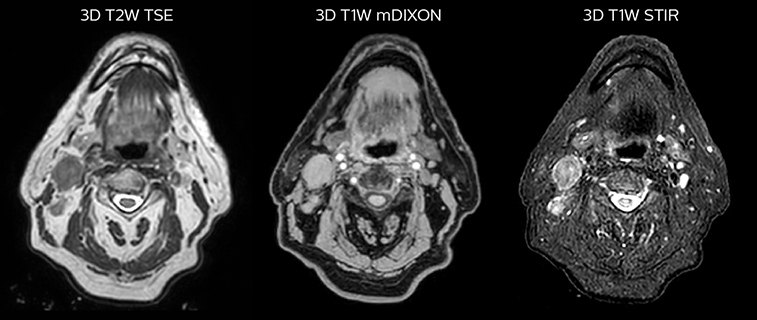

Epidermoid carcinoma of the left tongue base

The patient was diagnosed with an epidermoid carcinoma of the base of the left invading the amygdala lodge and the amygdaloglossal groove. Radiochemotherapy with curative aim was prescribed with a dose of 70 Gy for the tumor, 66 Gy on the suspicious nodes and 56 Gy on the elective drainage areas - in 33 fractions.

T2W 3D, 3D STIR and mDIXON MRI scans.